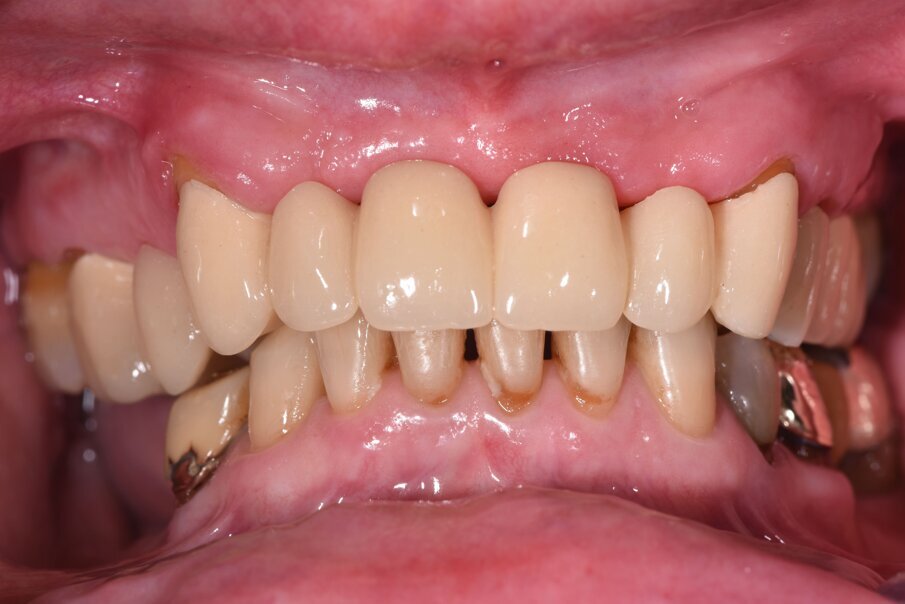

Il caso clinico descrive una situazione complessa di una paziente trattata con radioterapia 5 anni prima per un carcinoma della laringe, in conseguenza del quale era stato rimosso l’intero gruppo incisivo superiore sostituendolo provvisoriamente con una protesi parziale rimovibile stabilizzata con ganci a filo sui canini (Fig. 1). La paziente di 59 aa presentava inoltre delle protesizzazioni fisse nel quadrante I° e III° su elementi naturali, entrambe con vistose infiltrazioni e scheggiature che rendevano i manufatti incongrui. Lo stato parodontale iniziale presentava un sondaggio medio (Tab. 1) spesso associato a mobilità di vario grado e per taluni elementi era presente anche sanguinamento. All’esame obiettivo si evidenzia una complessa situazione clinica riportata di seguito in Tabella 2.

Fig. 1_Foto iniziale con il provvisorio rimovibile in posizione. La presenza di una flangia in resina consente un maggior supporto labiale.